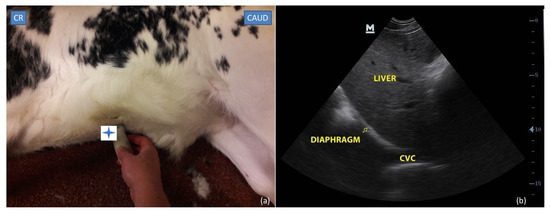

2.3.1. Subxiphoid Window

2.4.1. Subxiphoid Window